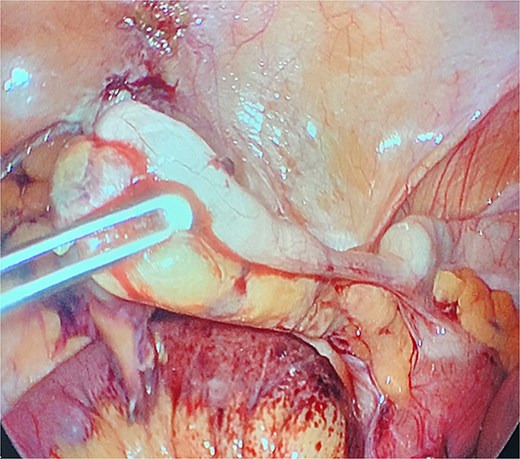

Due to imaging findings and ongoing clinical concern for impending bowel compromise, the patient was taken to the operating room urgently and underwent a diagnostic laparoscopy. Intraoperatively, the appendix was found to be inflamed at the tip and it was adherent to the lateral abdominal wall (Fig. 3). The appendix was forming a band encircling a loop of small bowel, resulting in a mechanical obstruction (Fig. 4). Lysis of the adhesions was performed, successfully freeing both the appendix and the entrapped segment of small bowel (Fig. 5). The involved bowel segment appeared hemorrhagic but was not frankly ischemic, therefore bowel resection was not needed. A laparoscopic appendectomy was subsequently performed. The excised appendix measured 7 cm in length (Fig. 6). The obstruction was resolved, and the patient tolerated the procedure well. She had an uncomplicated postoperative recovery. She started passing gas and tolerated oral intake on postoperative day 1. She was discharged on postoperative day 2. At her follow-up clinic visit, her incisions were well-healed. She reported normal bowel function, no abdominal pain, and was gradually resuming her regular activities. Overall, she was recovering well, with no concerns.

The appendix forming a band around the small bowel, causing small bowel obstruction (star).